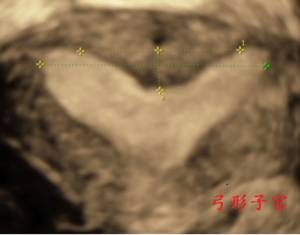

图:弓形子宫与纵隔子宫鉴别

图:弓形子宫三维成像

宫体轮廓无异常。由于宫底肌层略凹陷,在宫底水平的横切面上,子宫内膜暂被分开成两团,故呈“猫眼征”。而向下扫查时,“猫眼征”很快消失。

三维超声上宫腔形态基本呈倒三角形,双侧宫角内膜顶点与宫腔底部最低点连线的夹角为钝角;宫腔底部略凹陷,深度<10mm。若此夹角为锐角,且宫腔底部凹陷深度≥10mm,则诊断为纵隔子宫。